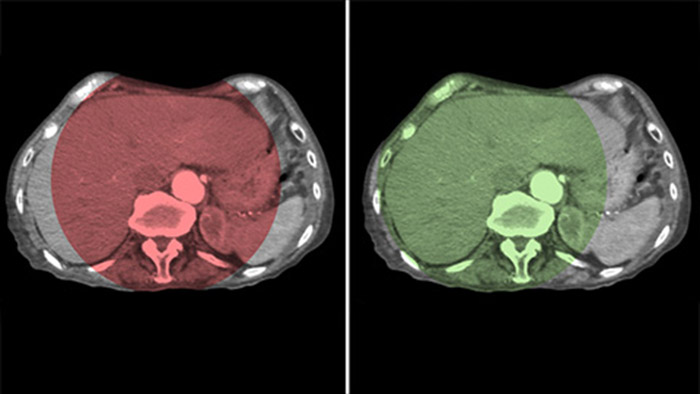

A CBCT Dupla permite a aquisição em 3D de uma fase arterial para visualizar estruturas vasculares e de uma fase pós-arterial (tardia) para visualizar o acúmulo do meio de contraste, em uma única etapa automática.5

O Dual View permite a visualização simultânea de dois conjuntos de dados da CBCT. Tanto a fase arterial quanto a fase tardia podem ser exibidas uma ao lado da outra ou em uma única exibição de sobreposição fundida.